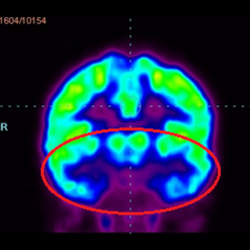

細(xì)胞治療前 PET CT 掃描顯示神經(jīng)組織中的藍(lán)/黑色區(qū)域,表明腦癱引起的大腦損傷。

腦癱細(xì)胞療法, 腦癱治療

細(xì)胞治療后,藍(lán)色和黑色區(qū)域減少,并且看到更活躍的區(qū)域。這表明損傷減少并改善了大腦功能。